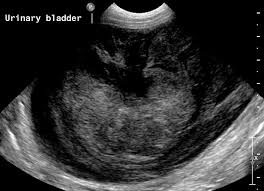

Small Animal Abdominal Ultrasonography The Urinary Tract Urinary Bladder Urethra Today S Veterinary Practice from todaysveterinarypractice.com It is fortunate that the majority of people with bladder cancer have the lower grade, superficial form of the disease, which typically does not spread beyond the bladder. Bladder cancer in dogs accounts for about 1 percent of canine cancers. This type of bladder cancer in dogs most often spreads to local or. The pain may be significant in pets that have evidence of metastasis (spread) to the bones of the lower back and pelvis. Other signs of dog's bladder infection include painful urination, passing urine with a bad odor, pus or blood in the urine, changes in the color of the urine and inability to hold urine, which. Signs of bladder cancer in dogs. As you can see, these symptoms are very similar to those of a bladder infection or bladder stones. With more than 60 million dogs in the usa, deaths from urinary bladder cancer are increasing rapidly.